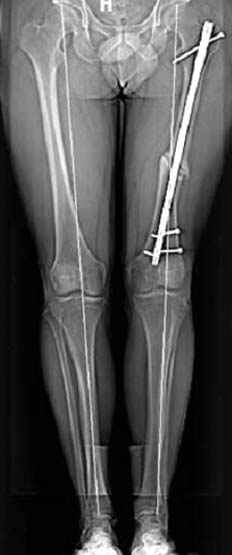

Несколько снимков из моей коллекции, чтобы разьяснить, почему мы до сих пор делаем различные варианты остеотомии.

На рисунке N1 предоперационный план лечения ложного сустава шейки бедра- линия ложного сустава, угол и направление введения импланта, клиновидная остеотомия в градусах и миллиметрах, второй снимок после коррекции, расчет, на сколько удлиняется конечность и размеры импланта;

N3 рисунок окончательный снимок, после операции моя рентгенограмма должен выглядеть примерно как эта картина. На N4 снимке клин перед удалением; N5 послеоперации 3 нед.; N6 окончательная рентгенограмма.

пластическая модель; и коррекция бедра аппаратом Илизарова.